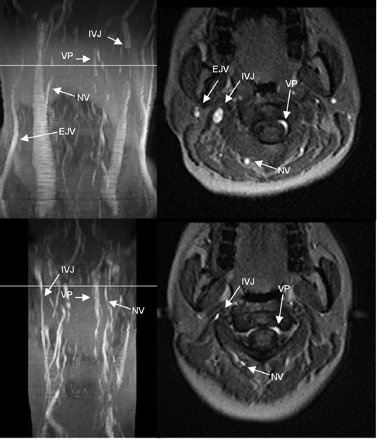

MIP (left column) and axial source images at the level of C2 in supine (top row) and sitting positions (bottom row) in a healthy volunteer. In the supine position, there is a high-grade stricture of the left IJV. The EJV, NV, and VP are visible. In the sitting position, only the right IJV is visible, but narrowed. The VP are prominent, and the NV can be identified.

Table 2 shows the delineation of the IJV and the presence or absence of strictures. A so-called “normal” CVBO pattern without any significant narrowing of 1 or 2 of the IJVs in the supine position was only seen in 7 volunteers (Figs 1 and 2). The other 8 volunteers had significant strictures of at least 1 IJV in the superior portion (Figs 3 and 4). In 3 of these 8 volunteers with a significant stenosis of the IJV in the supine position, the IJV was only delineated in the sitting position on both sides and in 2 volunteers on 1 side. It was, however narrowed compared with the findings in the supine position. The narrowing was homogeneous, and no stricture in the course of the IJV was observed. In the remaining 3 volunteers with a significant stenosis of the IJV in the supine position, the IJV was not delineated in the sitting position.